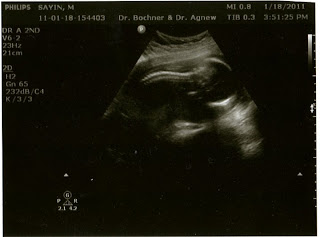

This week we went to get our second trimester anatomy scan. This appointment basically entailed an ultrasound specialist taking a longer look at the baby via the ultrasound machine and a computer. Then she would put measurements into the computer to figure out how big the baby is and how the baby is developing. Everything looked great and it was awesome to see the baby was healthy and growing!